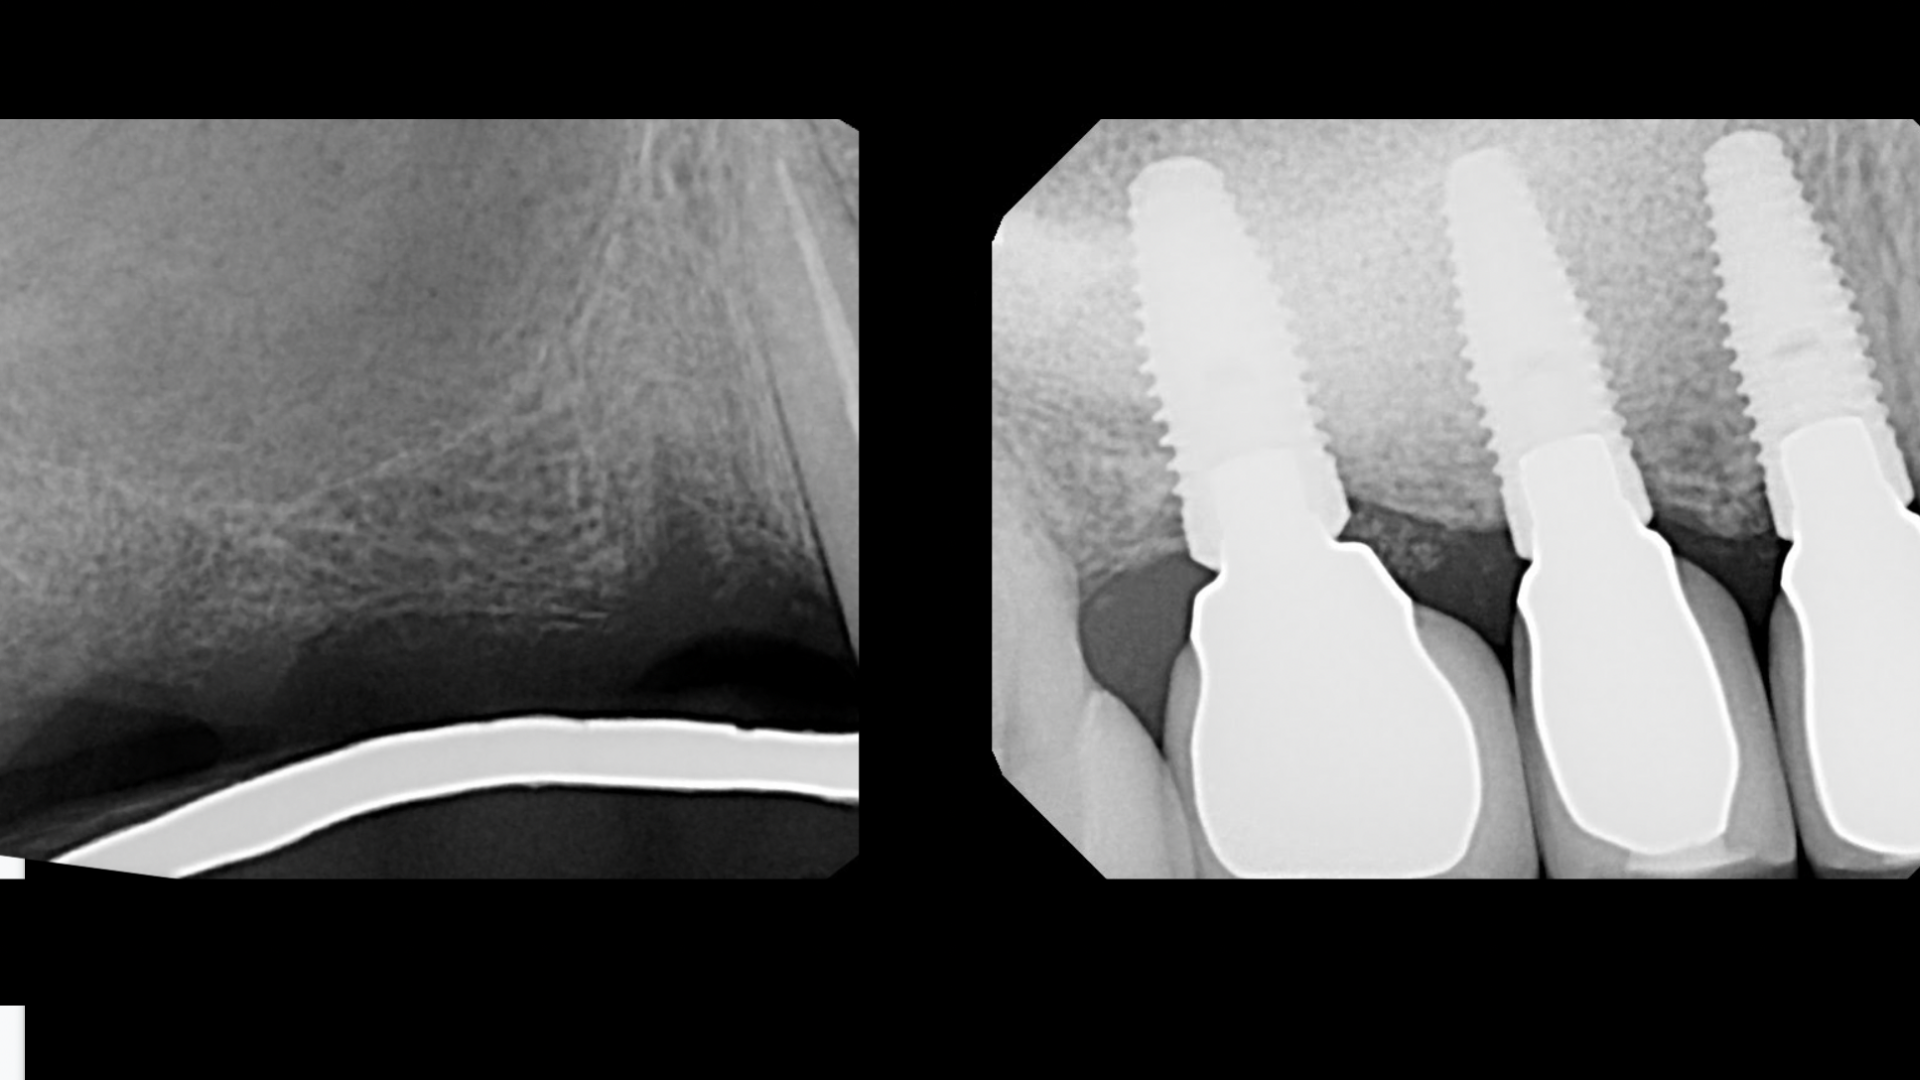

- How to diagnose the exact sinus lift method for each implant patient

- When a crestal sinus lift is indicated.

- When a lateral window sinus lift is indicated

Because about 50% of all upper molar implants need some sort of sinus lift.